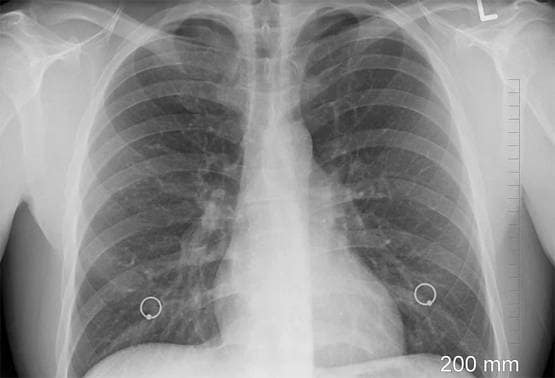

स्टडी में कहा गया है कि यह बदलाव कोरोना वायरस के स्पाइक प्रोटीन के हिस्से में देखा गया है. स्पाइक प्रोटीन के जरिए वायरस शरीर की कुछ कोशिकाओं को जकड़ कर रखता है. कोरोना वायरस की कंटीली संरचना ही ACE2 एंजाइम युक्त कोशिकाओं को निशाना बनाती है. ACE2 एंजाइम फेफड़ों में पाया जाता है. वैज्ञानिकों को अब तक यही जानकारी थी और वे ऐसी एंटीबॉडीज पर काम कर रहे थे जो कोरोना वायरस से लड़ने में सक्षम हो. लेकिन अचानक वायरस की संरचना में बदलाव होने से वैज्ञानिकों को नए सिरे से मेहनत करनी पड़ सकती है.

इस हाइड्रोजन बॉन्ड के बिना, हो सकता है कि वायरस फेफड़ों में पाए जाने वाले ACE2 या एंजियोटेंसिन परिवर्तित एंजाइम -2 के साथ अपनी पकड़ मजबूत नहीं करे. यानी कोरोना वायरस के अटैक करने का तरीका बदल सकता है.